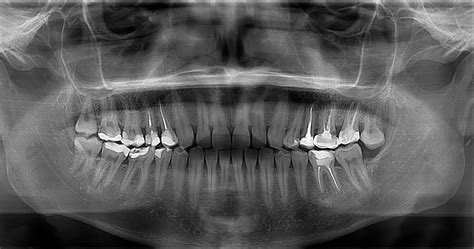

¿Qué Aspecto Tiene una Caries en una Radiografía?

La desmineralización y destrucción de las capas del diente se observa como una imagen radiolúcida (zona negra alrededor/dentro del diente). En la imagen que señala la flecha vemos una imagen radiolúcida (oscura) que indica la falta de material dental, la presencia de una zona “hueca”: Caries.

Es importante tener en cuenta que el diagnóstico temprano de las caries repercutirá en un mejor pronóstico del diente. En obturaciones antiguas (empastes/reconstrucciones) controlaremos que los márgenes de las restauraciones estén correctos, ya que en el material artificial no se producirán caries, pero en el tejido dental de alrededor sí podrían aparecer filtraciones.

¿Cómo se Identifica una Infección Dental en una Radiografía?

Aunque no verás directamente la infección como tal, lo que sí se puede observar son señales claras de que existe un problema, como zonas oscuras cerca de las raíces de los dientes. Por ejemplo, un absceso dental, que es una infección común, aparece en la radiografía como una sombra oscura alrededor de la raíz del diente afectado. Esta mancha oscura indica que la infección está causando daño al hueso que rodea al diente.

¿Qué se Puede Ver Exactamente?

- Abscesos dentales: Son acumulaciones de pus por una infección. En la radiografía suelen aparecer como manchas oscuras cerca de la raíz del diente.

- Pérdida de hueso: Si la infección ha llegado al hueso que sostiene el diente, se puede ver que esa zona está más “vacía” o con menos densidad.

- Caries profundas: Aunque una caries no es una infección por sí sola, si llega a la parte interna del diente (la pulpa), puede causar inflamación o infección, y eso también se nota en la radiografía.

- Problemas en las encías (como la periodontitis): Cuando hay infección en las encías, también se puede observar si hay pérdida ósea alrededor de los dientes.